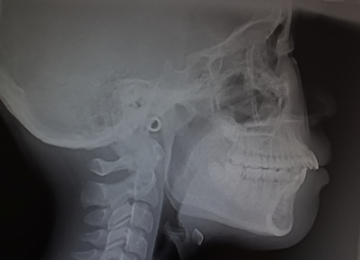

セファロ分析による精密な矯正診断

2)セファロ分析による精密な矯正診断

矯正治療では、歯並びだけでなく顎の骨格やバランスを正確に把握することが重要です。当院ではセファロ(頭部X線規格写真)を用いた分析を行い、歯や顎の位置関係、骨格のバランスなどを詳しく確認しています。これにより、見た目の歯並びだけでなく、噛み合わせや顔全体のバランスまで考慮した治療計画を立てることが可能になります。患者様一人ひとりの骨格に合わせた矯正治療を行うことで、より安定した治療結果につなげていきます。